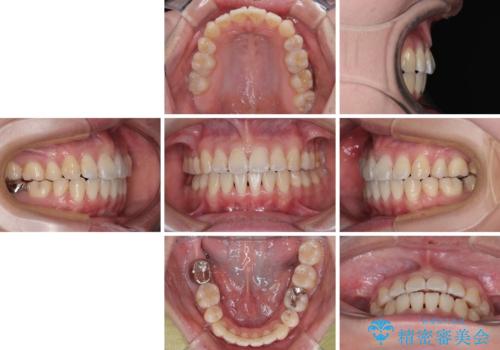

舌突出癖の改善トレーニングは、仕上がり、治療期間、そして治療後の後戻りに大きな影響を及ぼします。

トレーニングをしっかりと行っていただいたため、スッキリとした口元に仕上がりました。

- 1年8ヶ月

- 10-30回